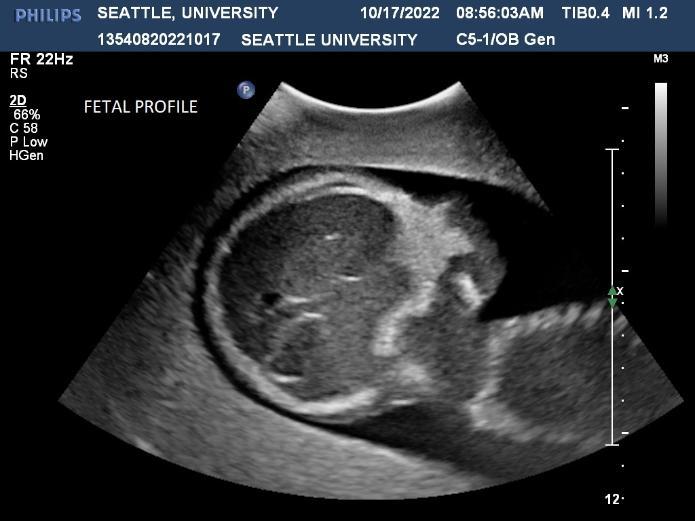

Ultrasound is a non-invasive diagnostic tool that uses high-frequency sound waves to propagate images of organs and tissues within the body. The Diagnostic Ultrasound program at Seattle University offers three distinctive track specializations in General (abdomen extended, OB/GYN) Vascular and Cardiac sonography.